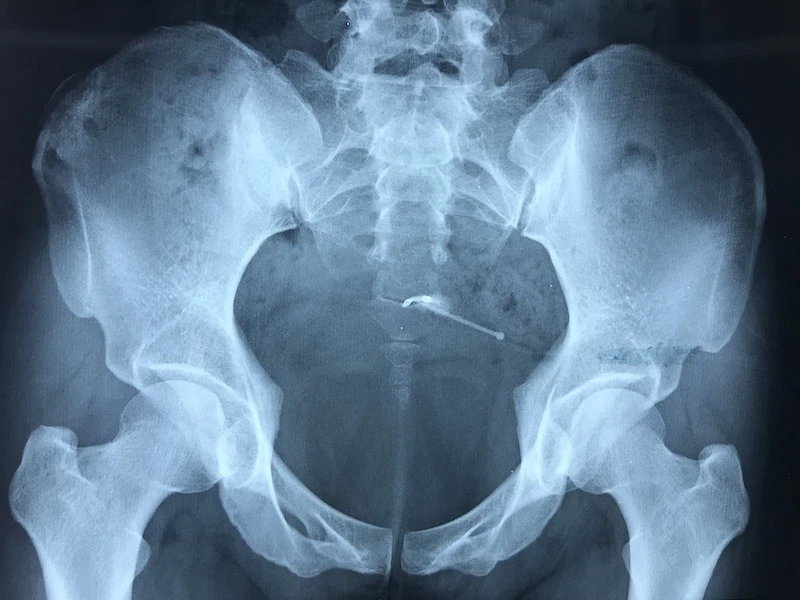

Hình ảnh X-quang cho thấy vòng chữ "T" nằm ở bàng quang chị N. Ảnh: HẢI DƯƠNG

Tiến hành chụp cắt lớp vi tính ghi nhận dụng cụ tránh thai lạc chỗ vùng ngoài tử cung cạnh thành trên, xuyên thành bàng quang. Các BS đã hội chẩn và chỉ định phẫu thuật lấy vòng ra. Chiếc vòng được bao chặt bởi các cơ xung quanh, đó là lý do khi siêu âm không phát hiện được.